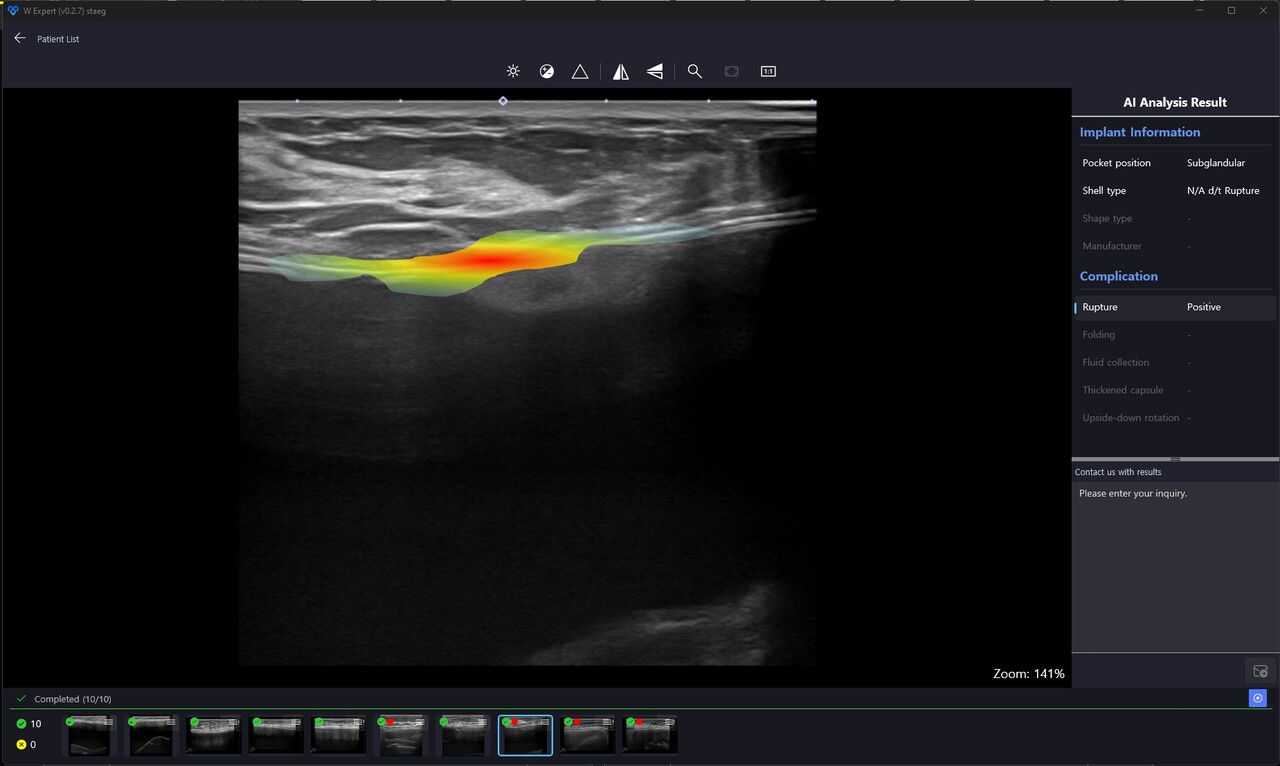

더블유닷에이아이의 'W Expert'는 초음파 이미지를 이용한 인공유방보형물 구별 및 부작용 진단 AI 솔루션이다. 일반 여성과 보형물이 있는 환자에서 보형물과 관련한 정보 및 다양한 부작용을 진단해 유방 검진 의사들에게 완전한 유방관련 AI 서비스를 제공하고자 개발된 서비스다. 현재 국내 20여개의 병·의원에서 연구버전을 사용하고 있다.

여성암 1위인 유방암 진단 시 보형물을 삽입한 환자에서 파열이나 구축과 같은 보형물과 관련한 정확한 진단이 필요하다. 이러한 점에서 인공유방진단 솔루션 W Expert는 세계 각국의 다양한 병원 환경에 맞춰 여러 버전의 솔루션이 개발되고 있다. 서비스는 설치형, 클라우드형, SDK(소프트웨어 개발 키트), API(응용 프로그램 프로그래밍 인터페이스) 방식 모두 지원한다. 다양한 의료영상저장정보시스템(PACS) 시스템과의 연동 서비스도 제공될 예정이다.